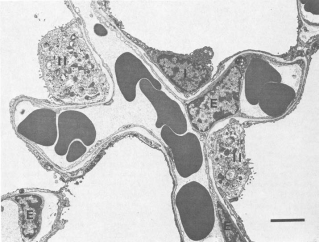

圖2 肺泡細胞的外觀:上皮I型細胞(I)、上皮II型細胞(II)和毛細血管內皮細胞(E)(bar=4μm)